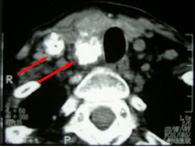

甲状腺髄様がんリンパ腺転移 |